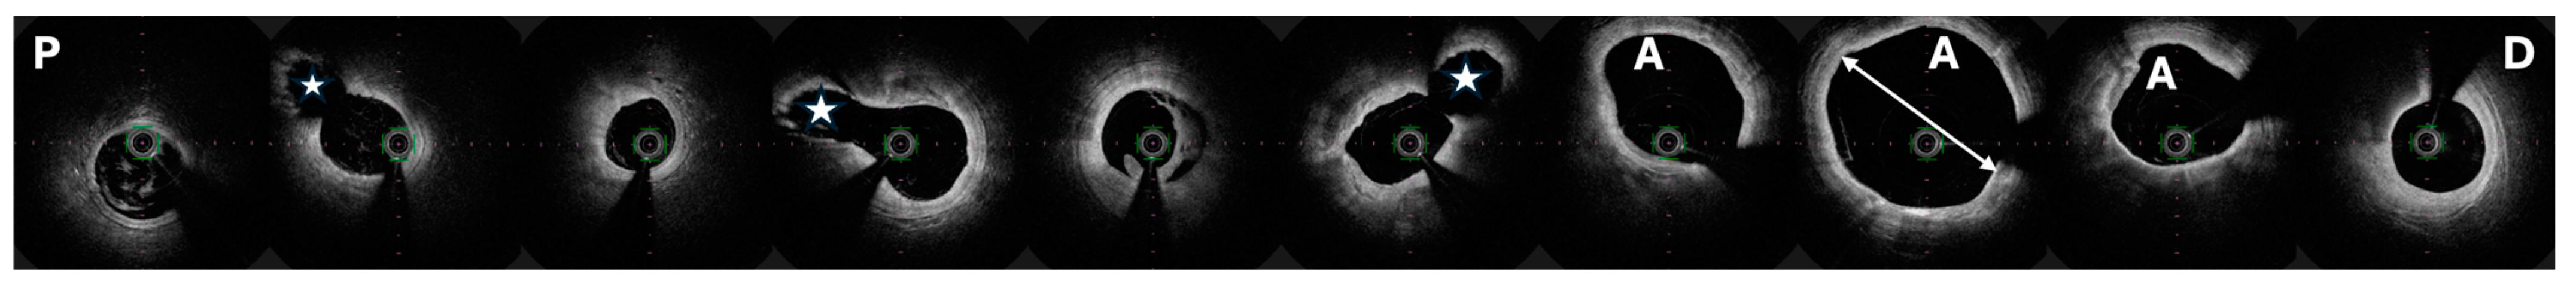

- Fathelbab, H.; Freire, S.J.C.; Jiménez, J.L.; Piris, R.C.; Menchero, A.E.G.; Garrido, J.R.; Fernández, J.F.D. Detection of spontaneous coronary artery spasm with optical coherence tomography in a patient with acute coronary syndrome. Cardiovasc. Revascularization Med. 2017, 18, 7–9. [Google Scholar] [CrossRef]